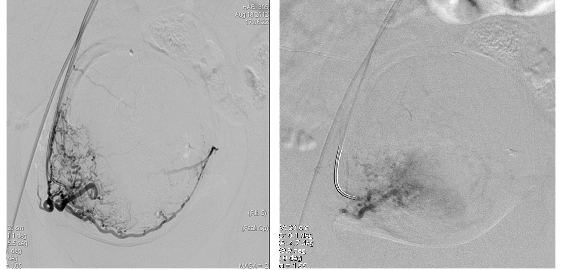

Primero diremos que el fin de la embolización es eliminar o disminuir el flujo vascular. Primero se realiza una arteriografía cerebral, sabiendo gracias a esto exactamente donde se ubica la lesión cerebral. Se elige un tipo de sistema de introducción femoral (se elige el tamaño) según variados aspectos técnicos y físicos de la persona a tratar. Luego de esto el sistema es conectado a una infusión de solución salina continua heparinizada, todo esto a través de una llave en forma de Y que permite el intercambio de solución salina. Se rasura, esteriliza y cubre con un paño y el anestesiólogo inyecta anestesia en la zona, luego se realiza un corte en la pierna, muy cerca de la ingle; en donde se encuentra la arteria femoral y se introduce el catéter ( que es un tubo largo, delgado y flexible que tiene generalmente el espesor de una hebra de spaguetti) con mucho cuidado. El médico guía el catéter hasta llegar a través de esta arteria al cerebro (guía el catéter inyectando a través de la arteria un líquido de contraste y así «iluminar» su camino hasta la lesión cerebral. Después de llegar al cerebro procede a buscar la lesión cerebral y hacer pasar a través del catéter el agente embolizante intentando ocluir por completo o parcialmente la lesión que está siendo tratada. Después de realizar esto, se procede a retirar el catéter y aplicar presión sobre la apertura en la arteria femoral, poniendo luego unas vendas (no necesita sutura). Después de la embolización el paciente debe permanecer acostado y en reposo para ser observado por sus médicos. Luego deberá permanecer de una a cuatro semanas hospitalizado, según sea su evolución.[5]